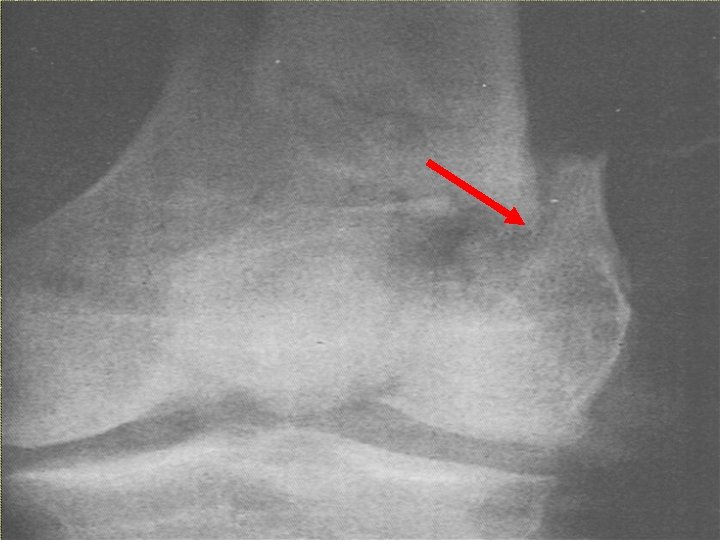

PATOLOGIE TRAUMATICHE A CARICO DELL’APPARATO LOCOMOTORE Frattura: rottura di una o più ossa (composta, scomposta, esposta, biossea, pluriframmentaria). Lussazione: fuoriuscita di una articolazione dal suo normale abitacolo (frattura – lussazione). Distorsione/distrazione: lesioni meniscali, capsulari e legamentose. Contusione: interessamento dei sottocute e della cute (ematoma). muscoli, Politrauma: interessa più organi e/o apparati. del